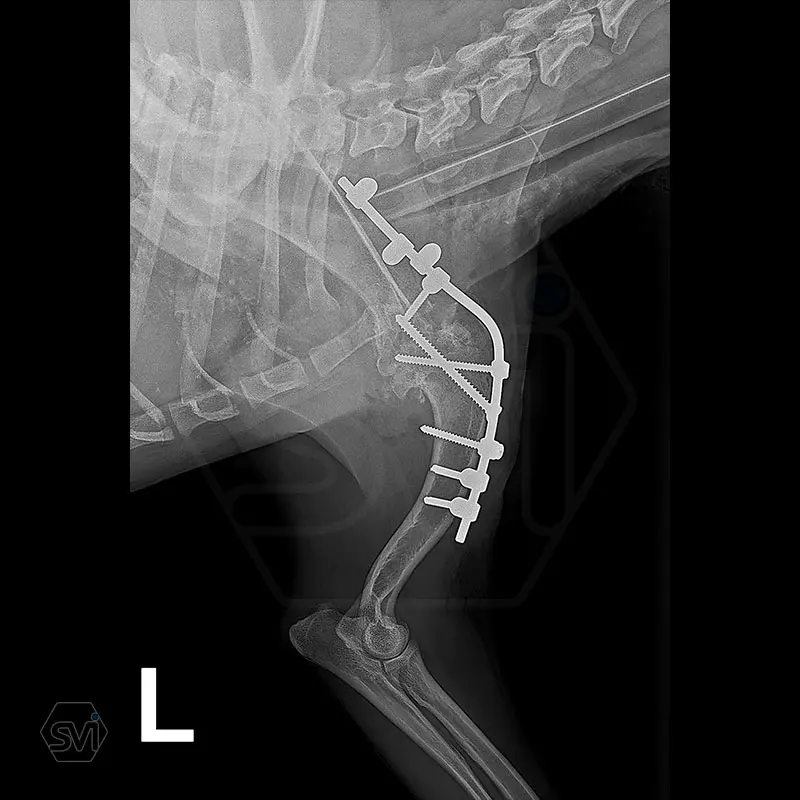

Arthrodesis is typically an area where the advantages of SOP-LC are clearly visible.

There is no weak point in bridging the joint, which is inevitable in a plate bridging. Another great advantage is that the clamps can be placed according to anatomical needs, on either side of the rod and the screws can be inserted in any direction. Maximum stability is provided by the locking clamps, which is especially advantageous in a thin bone (scapula) or a bone with a porotic or thinned cortex (leg that has been used less for a long time). We have used the system several times in reoperations due to a broken plate.

In our case, we created a shoulder arthrodesis on an 11-year-old 16kg female beagle dog with a 2.7 SOP-LC system and 4-4 clamps. The dog developed chronic arthritis and arthrosis, the biopsy did not confirm a tumor, only chronic inflammation.